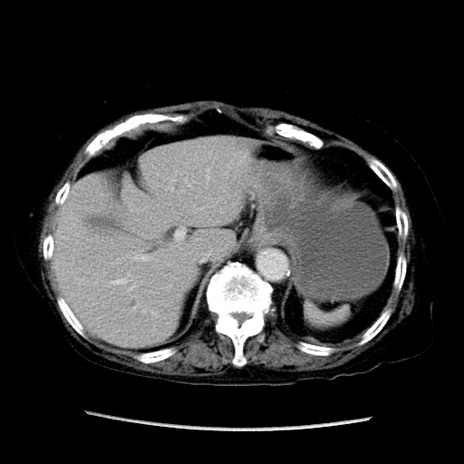

症例14(横断像)

【症例】 90歳代女性

【主訴】 腹痛・嘔吐

【現病歴】今朝から左側腹部痛を認めた。 経過観察していたが、嘔吐を認めたため来院。

【既往歴】 子宮癌術後

【身体所見】 意識清明、BP 127/54mmHg、P 98bpm Sp02 95%(RA)、BT 35.8°C、腹部平坦・軟腸ぜん動音聴取良好、右下腹部圧痛(+) 反跳痛なし

【データ】WBC 9800、CRP 0.46